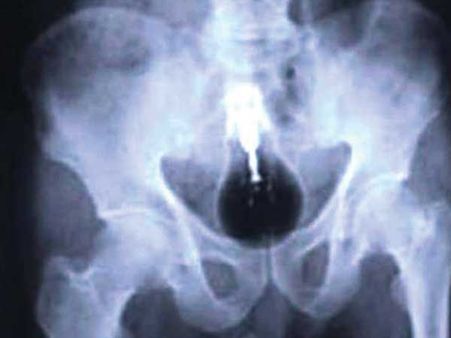

Light Bulb

Okay, it is true that a light bulb was found in the large intestine of a Pakistani prisoner. Now, you can let your imagination flow as to how did it even land there in the first place!